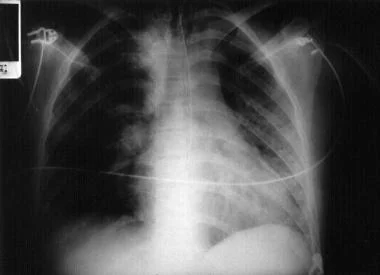

全血分析5分类是什么详解:吸入性肺炎表现、诊断与检测!│临床必备_https://www.jmylbn.com_新闻资讯_第4张

图4 右肺大面积吸入性肺炎患者胸片